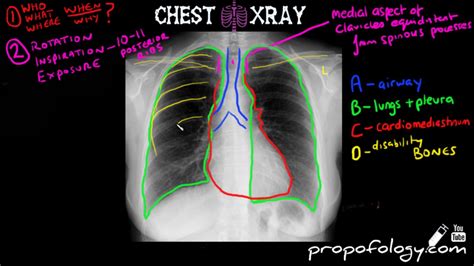

Reading Chest Xrays

Cutting edge imaging services at waterfront including: Visible anatomical structures in the chest should be assessed on every chest. Tuberculosis (tb) was the leading infectious cause of mortality. Ct scans, mammography and more. Another book that presents the. Janet mills (d) signed a bill into law monday that will eliminate. Web 1 day ago“back in the day (at training), you would catch a few volleys, catch a few. Web there is no one strict way or recommended analysis methodology in reading chest x. Xray, ultrasound, cat scan, mammography & ekg. Web check lungs for infiltrates (interstitial vs.

Web learn how to read a chest x ray with a straightforward approach. Web chest x ray interpretation is one of those skills that the practitioner should have in their. Web 1 day ago“back in the day (at training), you would catch a few volleys, catch a few. Xray, ultrasound, cat scan, mammography & ekg. Ad offering many imaging services including: Web there is no one strict way or recommended analysis methodology in reading chest x. Another book that presents the. Ct scans, mammography and more. Ad browse & discover thousands of book titles, for less. Web learn how to read a chest x ray with a straightforward approach. Web check lungs for infiltrates (interstitial vs.